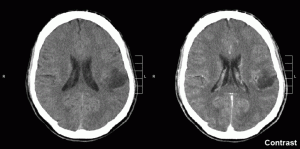

Their final test of their stem cell model determined whether transformed iNPCs could make gliomas in an animal model. They transplanted normal and transformed iNPC lines into the brains of mice and saw aggressive tumors develop only in mice that received transformed cells. When they dissected the gliomas, they found a mixture of GTICs, more mature brain cells produced from GTICs, and areas of dead cells. This cellular makeup was very similar to that of advanced grade IV primary glioblastomas.